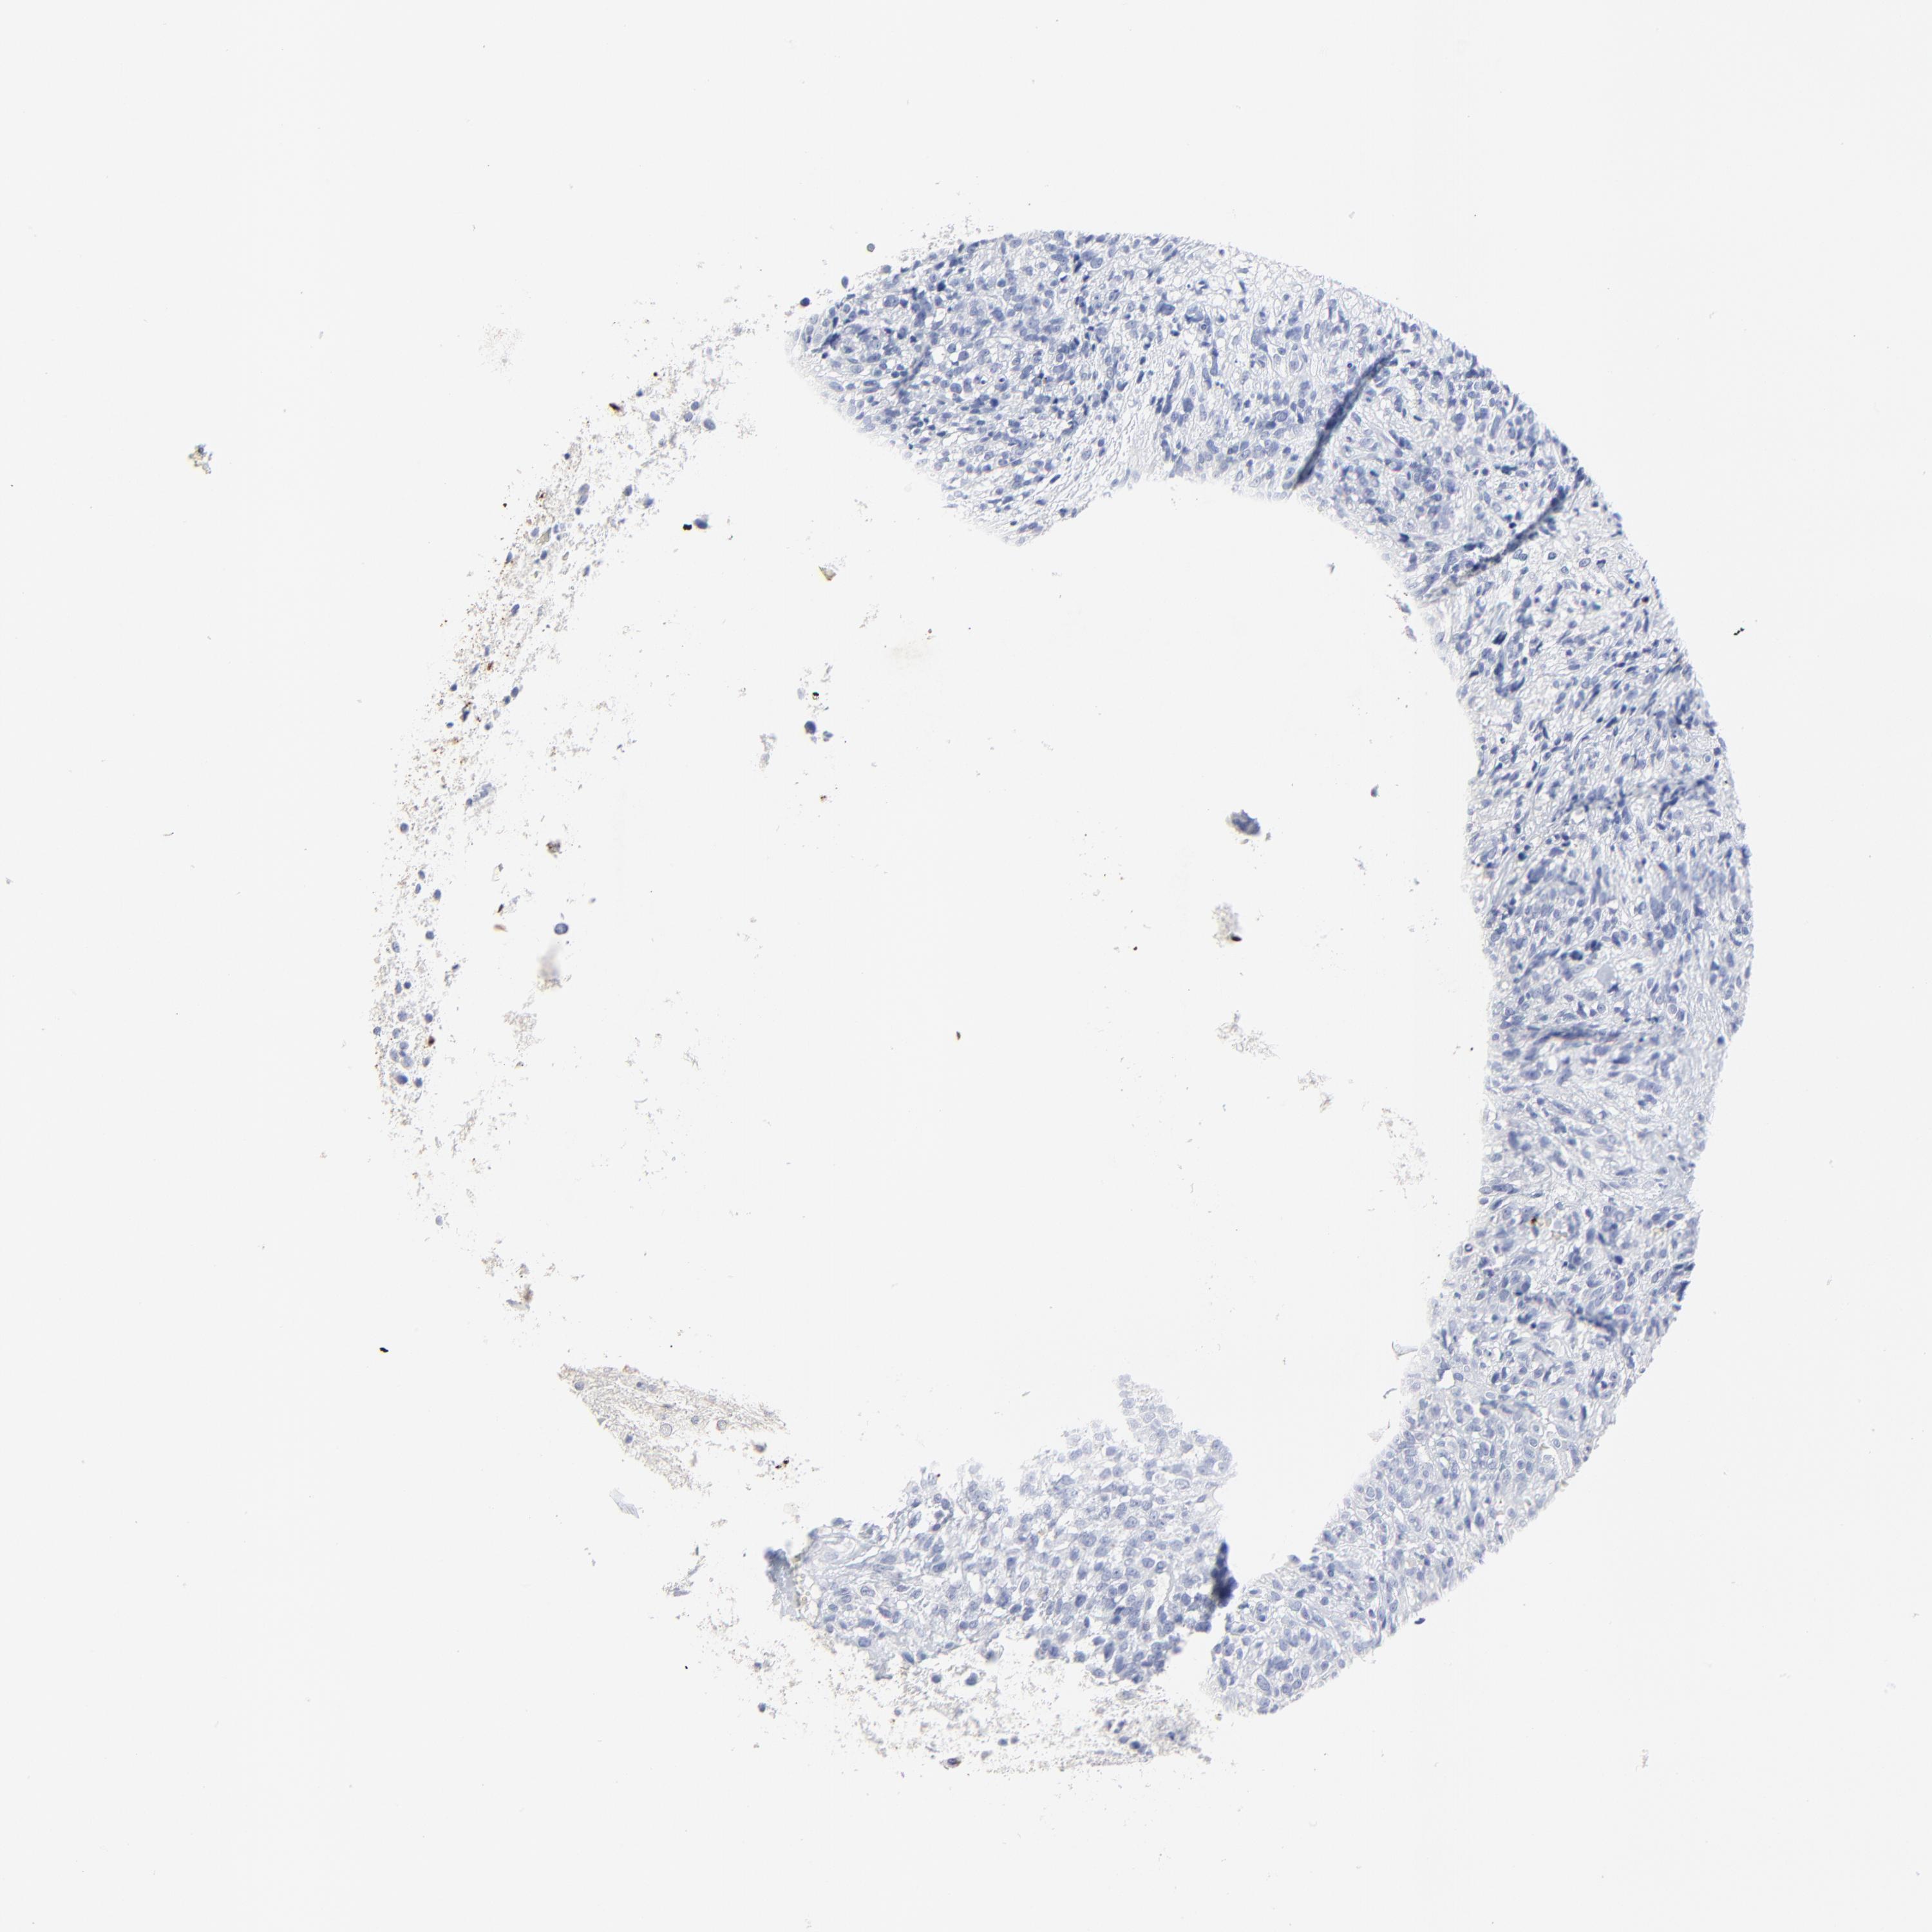

GLIOMA - Protein expressioni

A mouse-over function shows sample information and annotation data. Click on an image to view it in a full screen mode. Samples can be filtered based on level of antibody staining by selecting one or several of the following categories: high, medium, low and not detected. The assay and annotation is described here.

Note that samples used for immunohistochemistry by the Human Protein Atlas do not correspond to samples in the TCGA dataset.

Antibody stainingi

Antibody staining in the annotated cell types in the current human tissue is reported as not detected, low, medium, or high, based on conventional immunohistochemistry profiling in selected tissues. This score is based on the combination of the staining intensity and fraction of stained cells.

Each image is clickable and will lead to virtual microscopy that enables deeper exploration of all samples and also displays staining intensity scores, fraction scores and subcellular localization as well as patient and tissue information for each sample.

Antibody HPA002695

Antibody CAB016549

Antibody CAB016550

Glioma, malignant, High grade

Glioma, malignant, Low grade